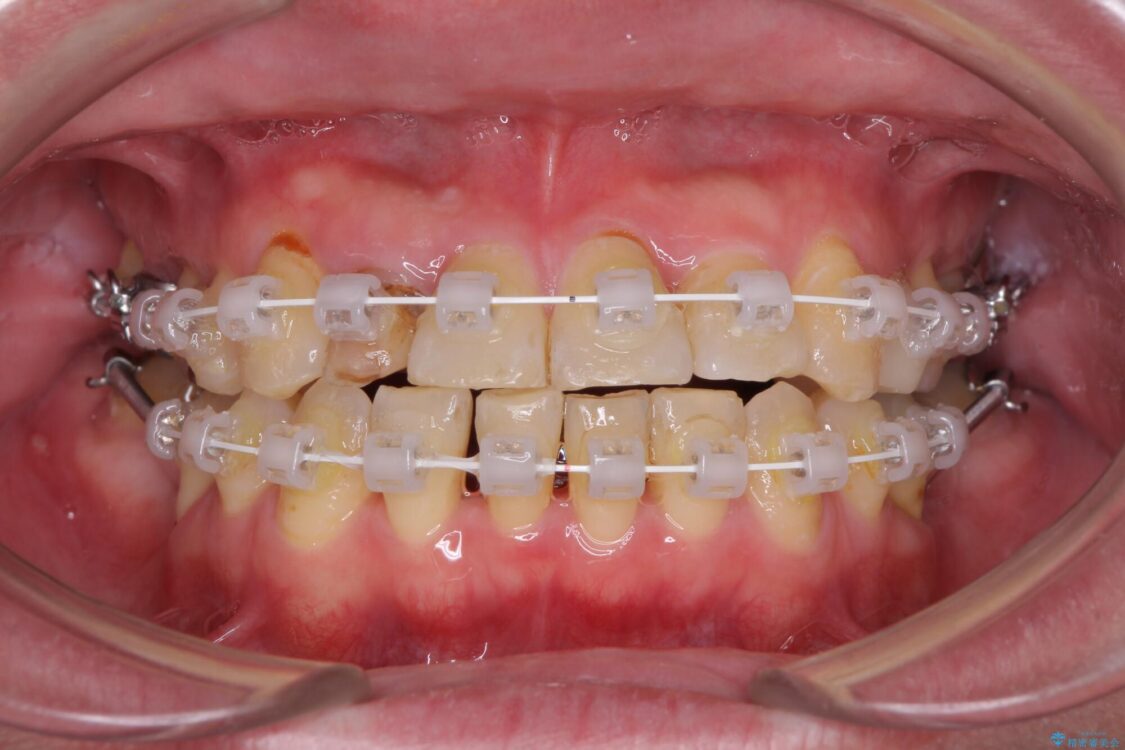

治療途中

• 割れてしまった奥歯とデコボコの前歯 矯正治療とインプラント治療 治療途中画像